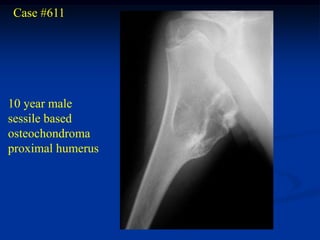

Case #611

10 year male

sessile based

osteochondroma

proximal humerus

Lateral view